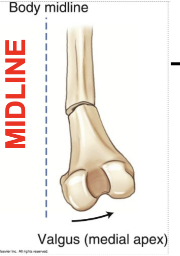

What angulation is this?

Valgus (eversion) deformity

distal fragment away from midline/apex towards (medial)